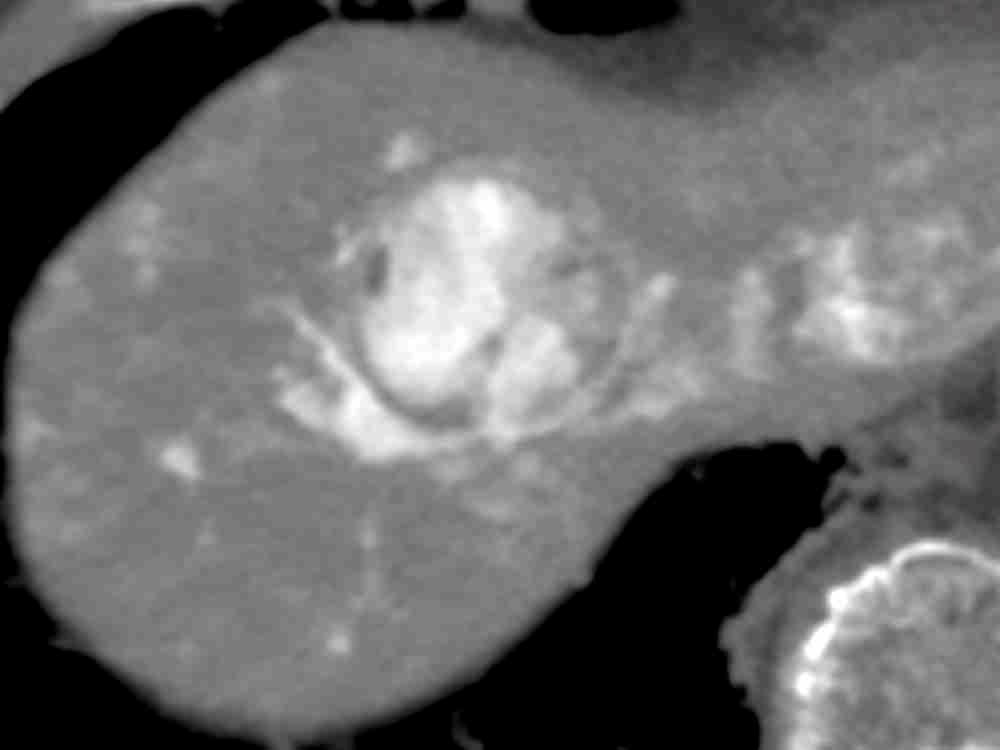

肝細胞癌はIVRに最も馴染みの深い癌で、標準治療の一つであるTACEはIVRの代名詞の一つとなっています。近年、肝細胞癌治療は複雑化しており、当IVR外来では、消化器内科とも連携し、TACEのみならず、RFA、動注療法、薬物療法などを取り扱います。是非、ご紹介ください。また、肝転移に対しても、同様の治療を行うことが可能です。

HCC 薬物療法